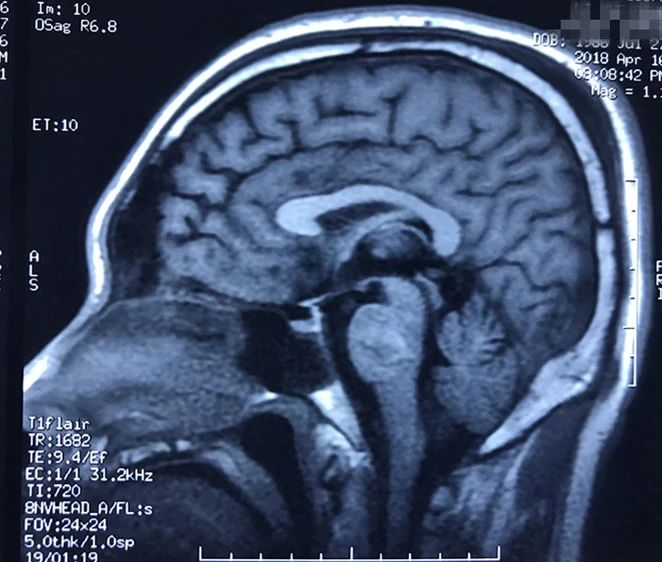

病人多发脑海绵状血管畸形,本次出血部位位于桥脑。第一次出血,术前偏瘫,转入我病房时为出血一月左右,采取颞下岩前入路切除脑干病变,术后病人肢体肌力较术前有提高,目前尚未出院。

本次手术资料:

术后磁共振显示脑干病变消失